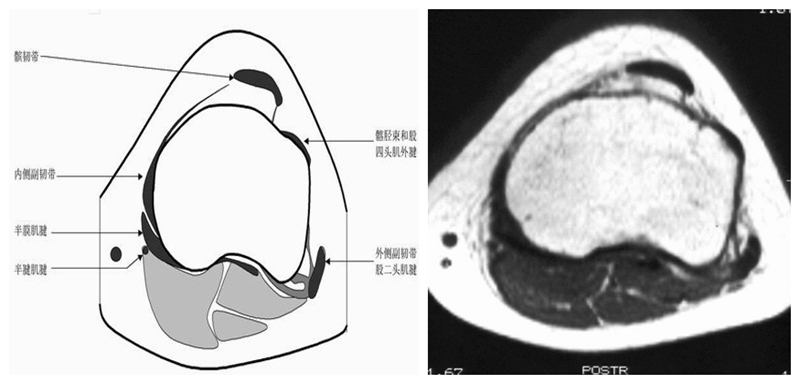

膝关节横断面MRI解剖

三维影像首选的方位,便于与CT比较,可准确地展现髌骨内外侧关节面。

横断面解剖第四层